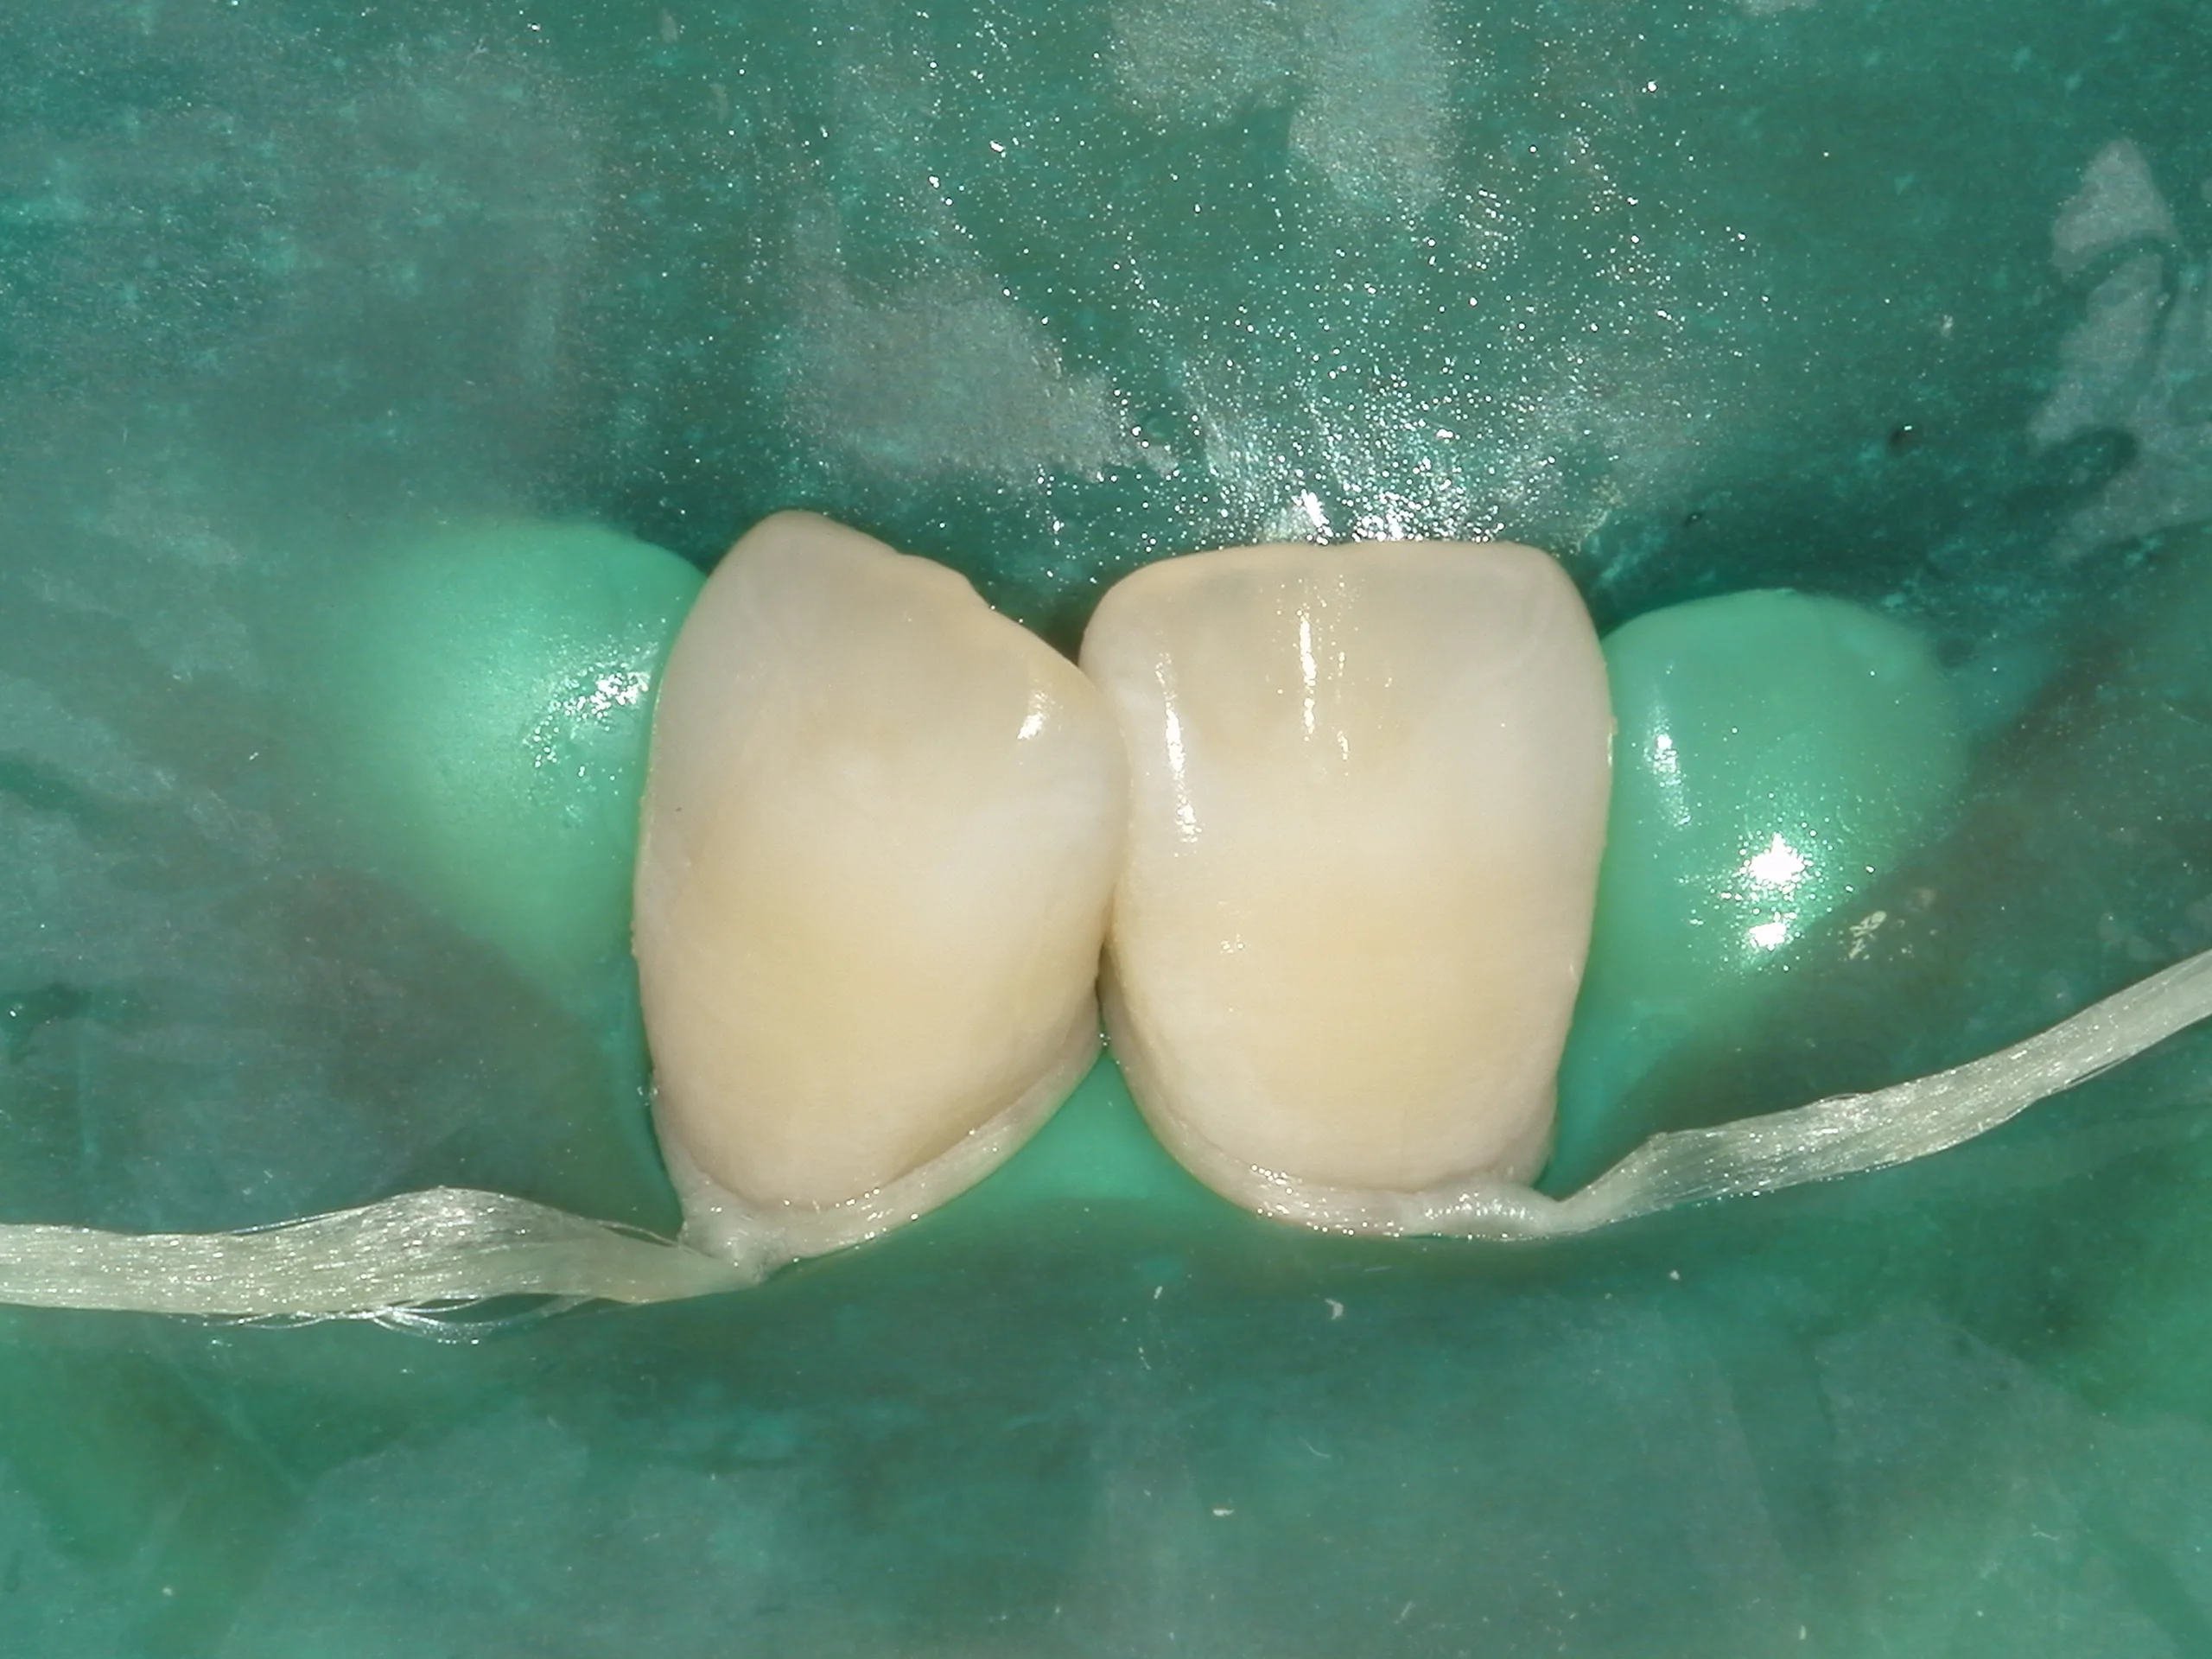

そしてホワイトスポットが消えたなと肉眼で判断出来たら、そこにICONを染み込ませて固めます。

固めたのがこちらになります。

ラバーダムを外した術前術後の写真はこちらになります。

随分と目立たなくなったのが分かるかと思います。

従来は切削が必要だった症例に対して、歯を削る量を抑えて対応できる場合があるのは、患者さんにとって意義のある選択肢になり得ると感じています(症例によって適応や効果には差があります)。